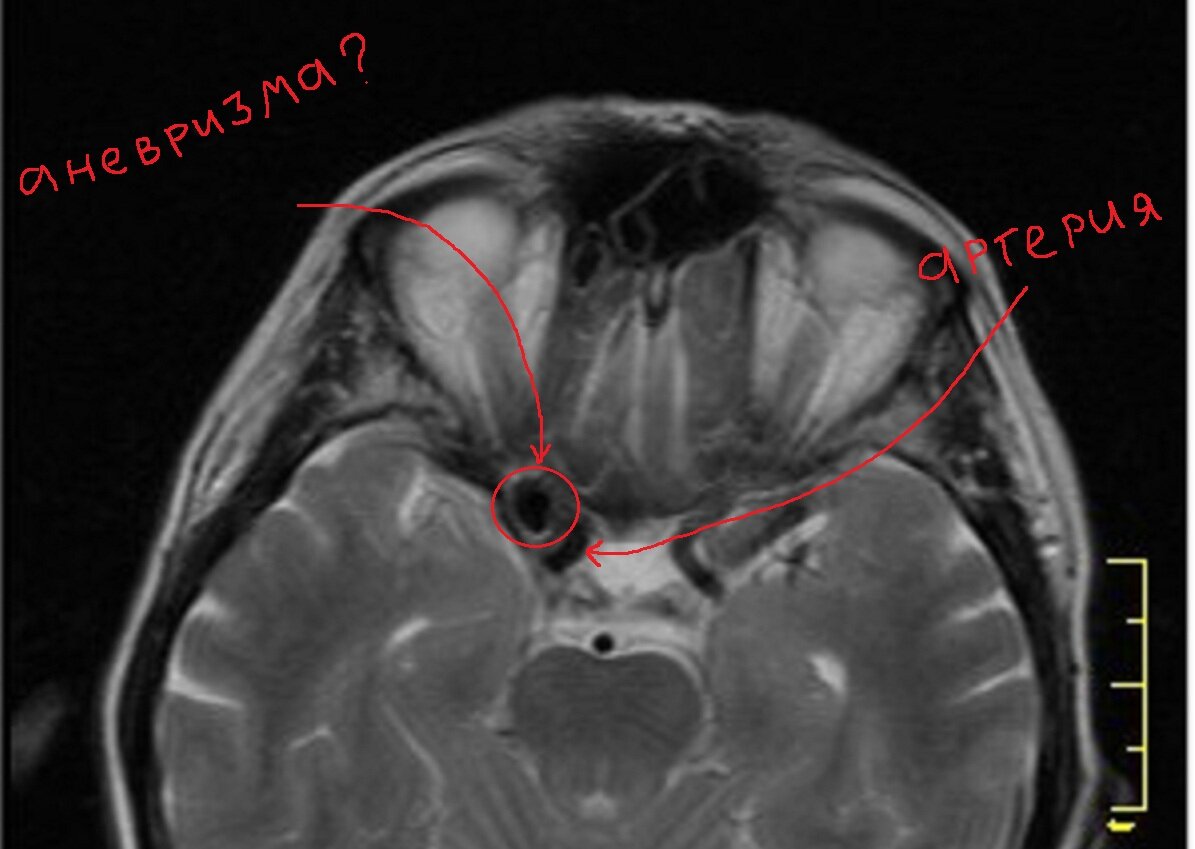

Диагноз аневризмы был поставлен по данным МРТ, размеры указаны довольно крупные – 12х8мм. Посмотрите картинку:

кровоток в артерии выглядит тёмным (к слову, этот феномен называется «пустотой потока», так выглядят на МРТ быстро текущие жидкости).

Наша грозная "аневризма" оказывается добавочной ячейкой основной пазухи, как и положено, заполненной воздухом. Воздух содержит мало протонов, и не даёт сигнала на МР изображениях.